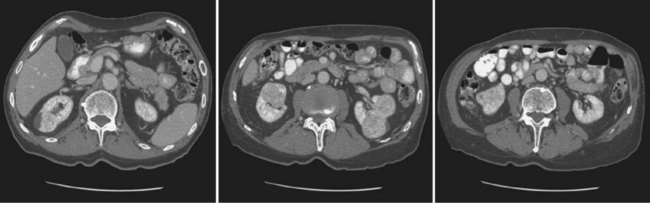

The Bosniak classification for renal cystic lesions, as reviewed in Table 51–1, is perhaps the most useful and widely employed method for characterizing renal cystic lesions and for assessing the likelihood of the presence of a concomitant malignancy within the cyst (Israel and Bosniak, 2005; Warren and McFarlane, 2005). In general, Bosniak class I, II, and IIF cysts are likely to represent benign lesions, thus requiring either no therapy or just continued radiographic follow-up, in the case of class IIF lesions (Fig. 51–1). These recommendations are based on a number of series published in the literature by Bosniak and others that include both radiographic as well as pathologic follow-up (Warren and McFarlane, 2005).

Figure 51–1 A, CT scan of a Bosniak I renal cyst. B, CT scan of a Bosniak II renal cyst. Note internal calcification. C, CT scan of a Bosniak IIF renal cyst. Several thin irregular septations are present within the cyst.